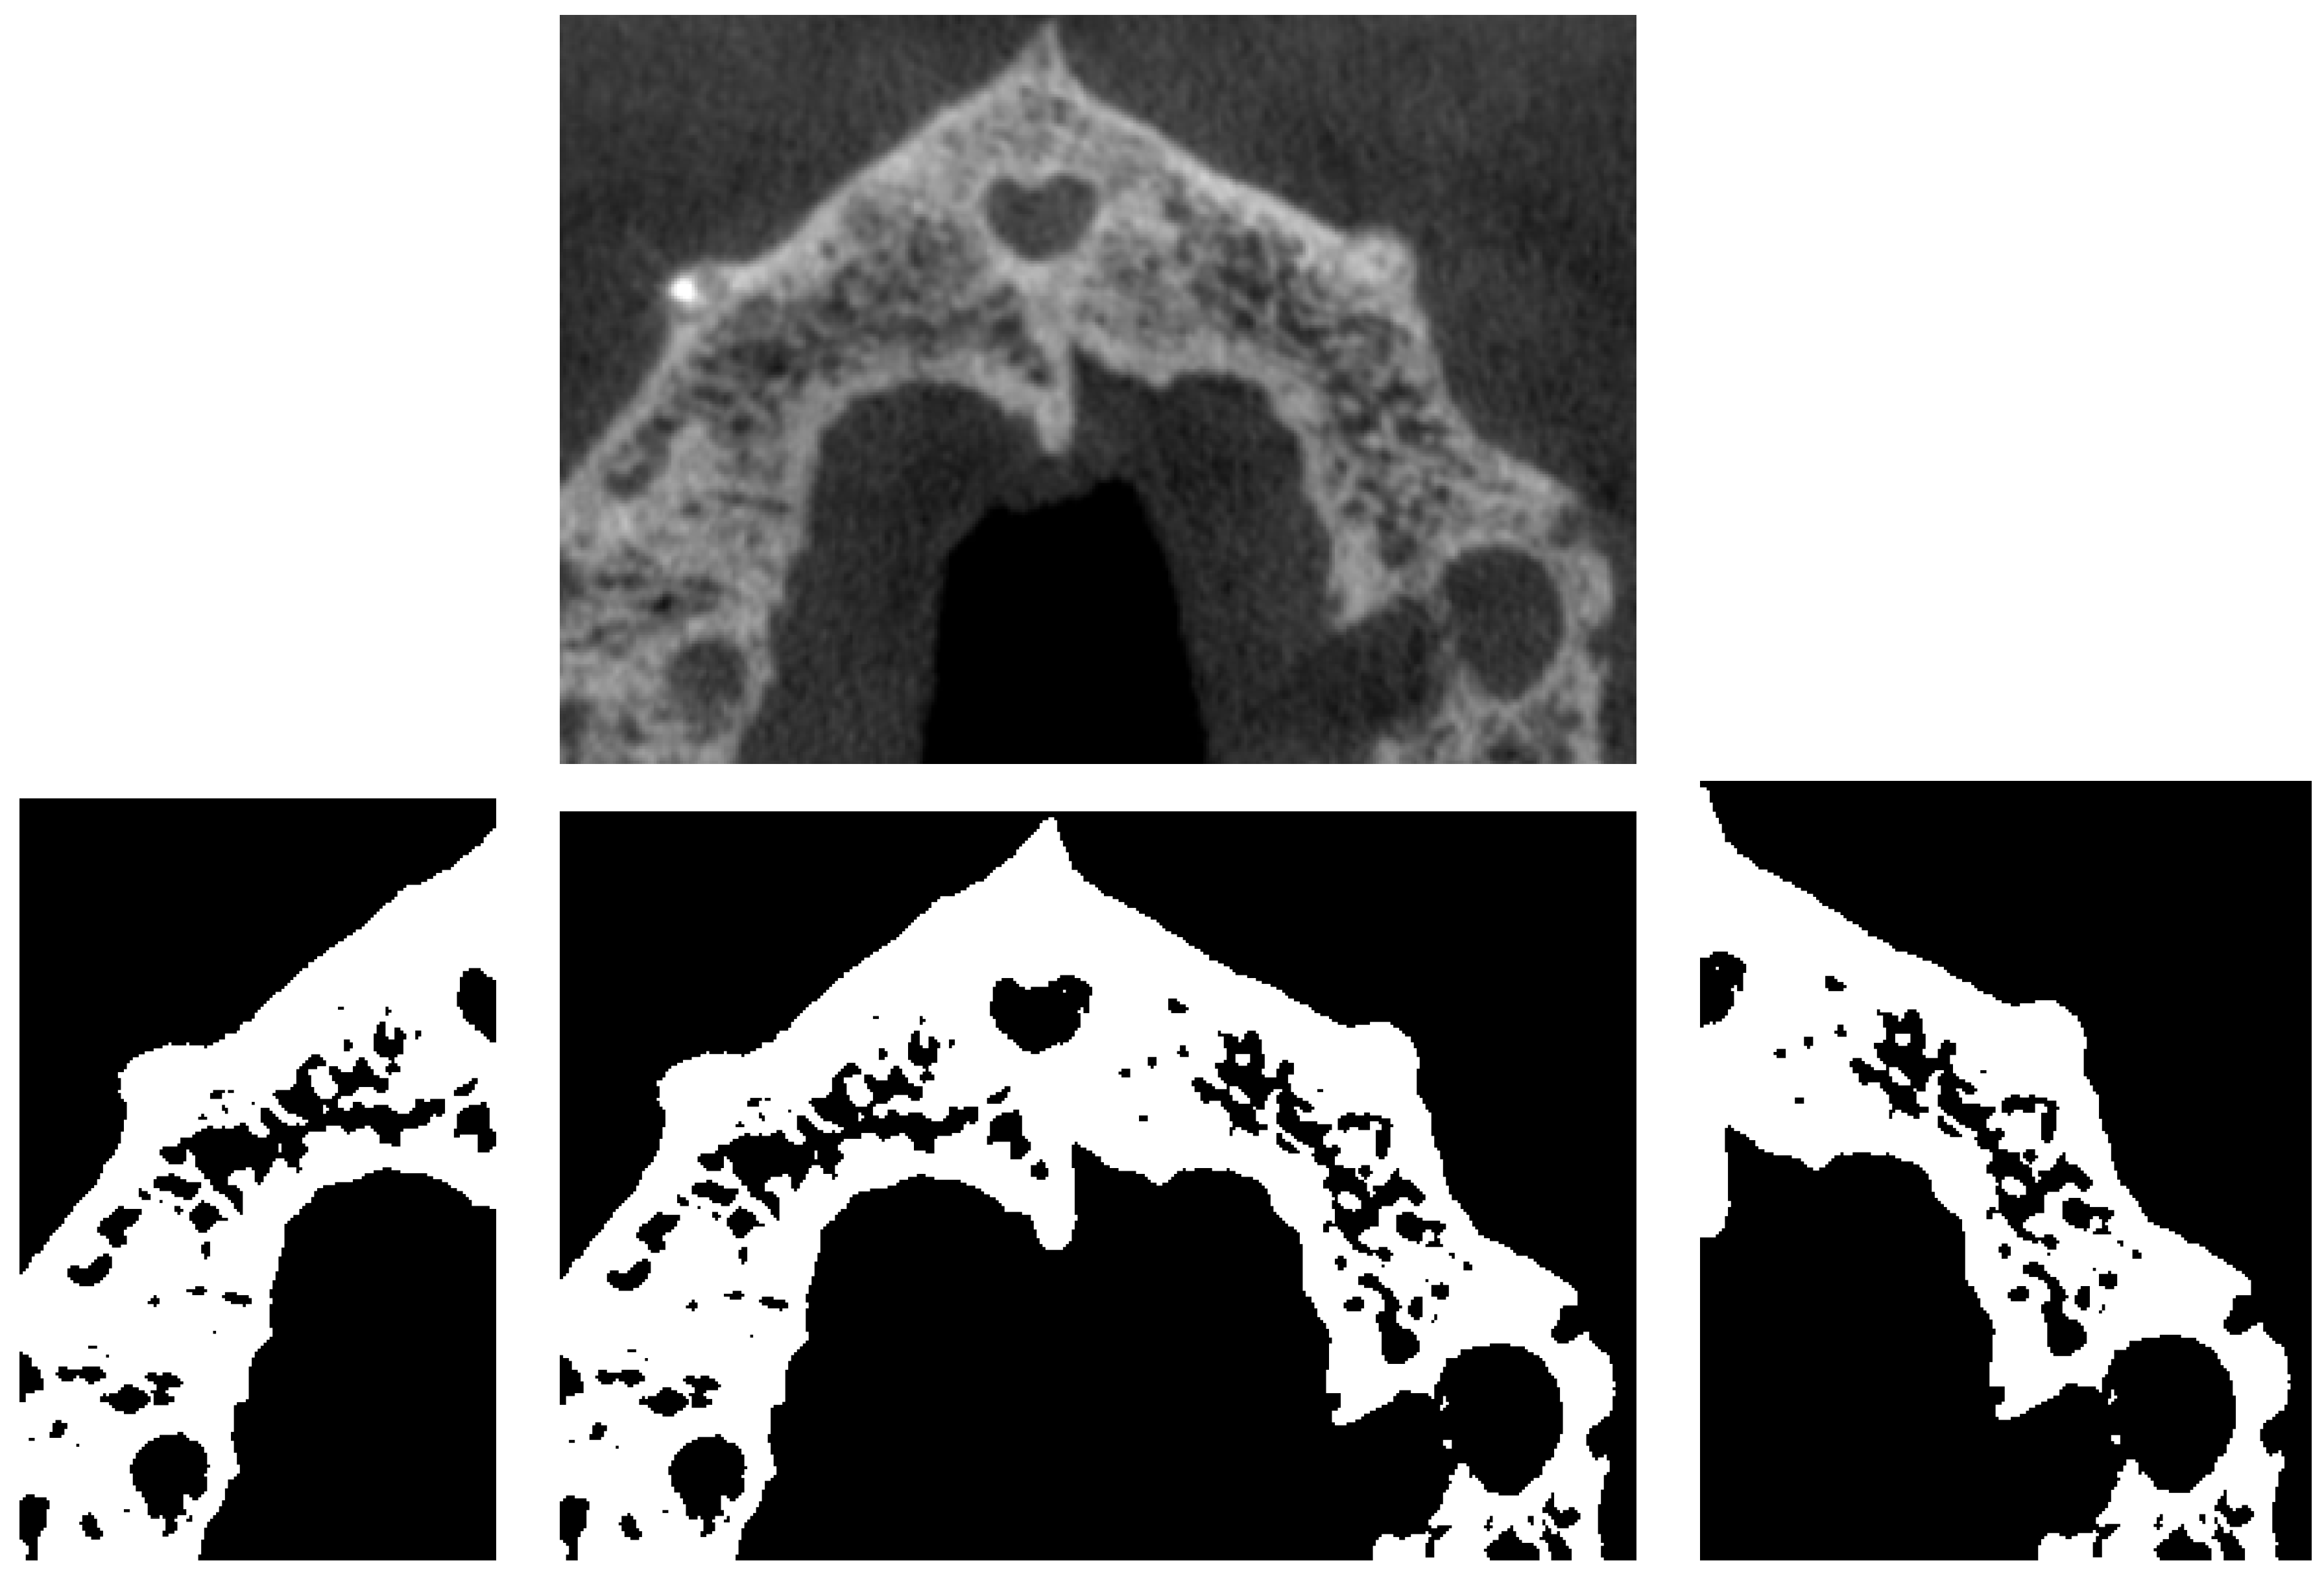

3.4. A First Step towards Symmetry

3.5. Fractal Dimension Analysis